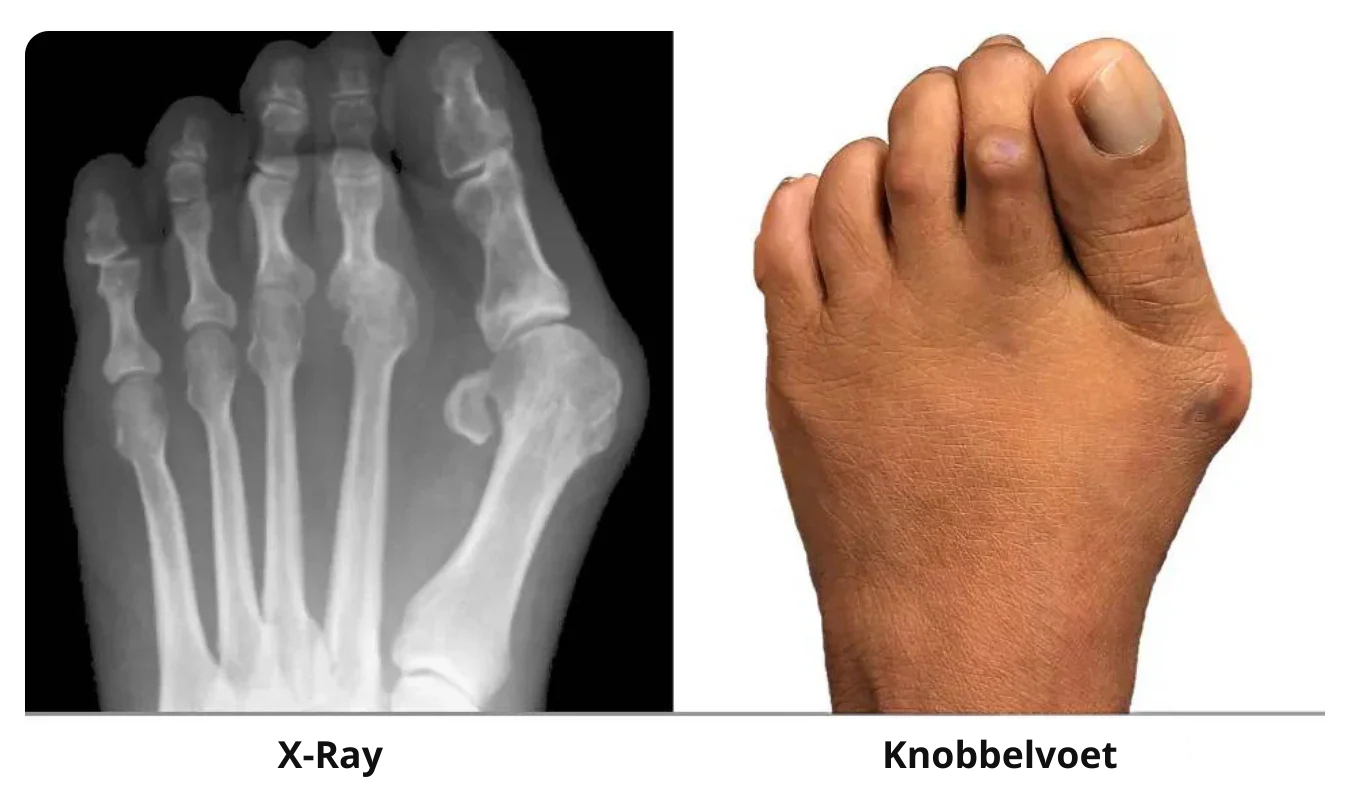

Die pijnlijke bult is niet zomaar "extra bot" dat chirurgisch verwijderd moet worden.

Wat er echt gebeurt is dat je grote teen ver uit zijn positie buigt.

De natuurlijke positie zou recht moeten zijn, net zoals de voeten van baby's eruitzien wanneer ze geboren worden.

De gevolgen? Het verstoort je dagelijks leven.

Zonder goede verzorging verergert de situatie—je tenen kunnen over elkaar heen gaan liggen, en problemen zoals hamertenen of botknobbels kunnen ontstaan.

Een scheefstaande teen herstelt niet vanzelf; deze verslechtert geleidelijk in de loop van de tijd.

Dit kan uiteindelijk leiden tot invasieve chirurgie, langdurige pijnmedicatie, of zelfs moeite met lopen.